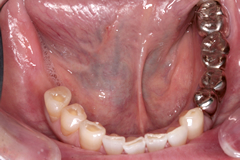

● インプラント治療の症例